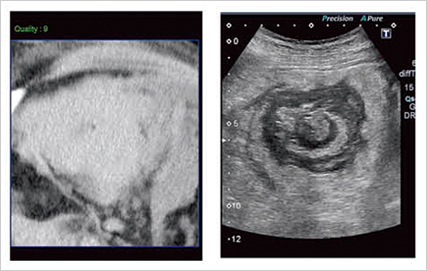

次に,急性虫垂炎症例のAplioXGとAplio500の比較画像を図3に提示する。図3上段はコンベックス型探触子(3.5MHz),中段はコンベックス型探触子(6.0MHz)のPrecision ImagingとApliPureで処理を行った画像だが,Aplio500ではスムーズな処理で鮮明に描出されていることがわかる。さらに,高周波リニア型探触子の8.0MHz(図3下段)においては,AplioXGでは表現できなかった虫垂壁の層構造と,内部に貯留した液体の性状が識別できるなど,Aplio500では「見えなかったものが見える!」と言えるほどに画質が向上していることがわかる。

図3 急性虫垂炎のAplioXG(a)とAplio500(b)の画像比較